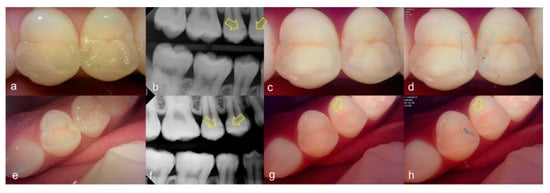

Evaluating proximal dental caries according to the QLF criteria and X-ray criteria, moderate positive correlation was observed (r = 0.63, p < 0.0001). Among the QLF parameters classified based on X-ray criteria, the |ΔFmax| value increased significantly as the score value increased from 1 to 4 (from 3.12 to 19.56). In particular, |ΔFmax| was about 5.7-fold higher for proximal dental caries score = 3 (17.64) than proximal dental caries score = 0 (3.12), and the maximum loss of fluorescence was 6.3-fold higher for the proximal dental caries score = 4 (19.56) (Table 2). The cut-off value of |ΔFmax| for detecting proximal dental caries (X-ray criteria scores 0 and 1 vs 2–4) was 5.95. The sensitivity, specificity and AUROC of parameter were 0.74, 0.73 and 0.81, respectively. However, the sensitivity, specificity and AUROC of the parameter ΔRmax were 0.83, 0.00 and 0.59 (Table 3). Representative images of QLF and bitewing radiograph of proximal dental caries are shown in Figure 6, Figure 7 and Figure 8.

Figure 6.

Proximal dental caries: (a–d) QLF caries score 0 (no fluorescence loss and no red fluorescence increase in occlusal surface (distal side)) and radiographic caries score 1 (radiolucency visible in the enamel) on #14 and QLF caries score 0 (no fluorescence loss and no red fluorescence increase in occlusal surface (mesial side)) and radiographic caries score 2 (radiolucency in the dentine but restricted to the outer 1/3 of the dentine) on #15; (e–h) QLF caries score 1 (fluorescence loss and red fluorescence present in occlusal surface (distal side)) and radiographic caries score 2 (radiolucency in the dentine but restricted to the outer 1/3 of the dentine) on #14 and QLF caries score 0 (no fluorescence loss and no red fluorescence increase in occlusal surface (distal side)) and radiographic caries score 2 (radiolucency in the dentine but restricted to the outer 1/3 of the dentine) on #15; (a,e): white-light image of QLF; (b,f): fluorescence image of QLF; (c,g): bitewing radiograph; (d,h): analyzed QLF image using QA2 software.

Figure 7.

Proximal dental caries: (a–d) QLF caries score 0 (no fluorescence loss and no red fluorescence increase in occlusal surface (distal side)) and radiographic caries score 3 (radiolucency extending to the middle 1/3 of the dentine) on #16; (e–h) QLF caries score 2 (fluorescence loss and red fluorescence glow extending around occlusal surface (distal side)) and radiographic caries score 3 (radiolucency extending to the middle 1/3 of the dentine) on #14; (i–l) QLF caries score 2 (fluorescence loss and red fluorescence glow extending around occlusal surface (distal side)) and radiographic caries score 3 (radiolucency extending to the middle 1/3 of the dentine) on #15; (a,e,i): white-light image of QLF; (b,f,j): fluorescence image of QLF; (c,g,k): bitewing radiograph; (d,h,l): analyzed QLF image using QA2 software.

Figure 8.

Proximal dental caries: (a–d) QLF caries score 0 (no fluorescence loss and no red fluorescence increase in occlusal surface (distal side)) and radiographic caries score 4 (radiolucency in the pulpal 1/3 of the dentine) on #26; (e–h) QLF caries score 2 (fluorescence loss and red fluorescence glow extending around occlusal surface (distal side)) and radiographic caries score 4 (radiolucency in the pulpal 1/3 of the dentine) on #25 (a,e): white-light image of QLF; (b,f): fluorescence image of QLF; (c,g): bitewing radiograph; (d,h): analyzed QLF image using QA2 software.